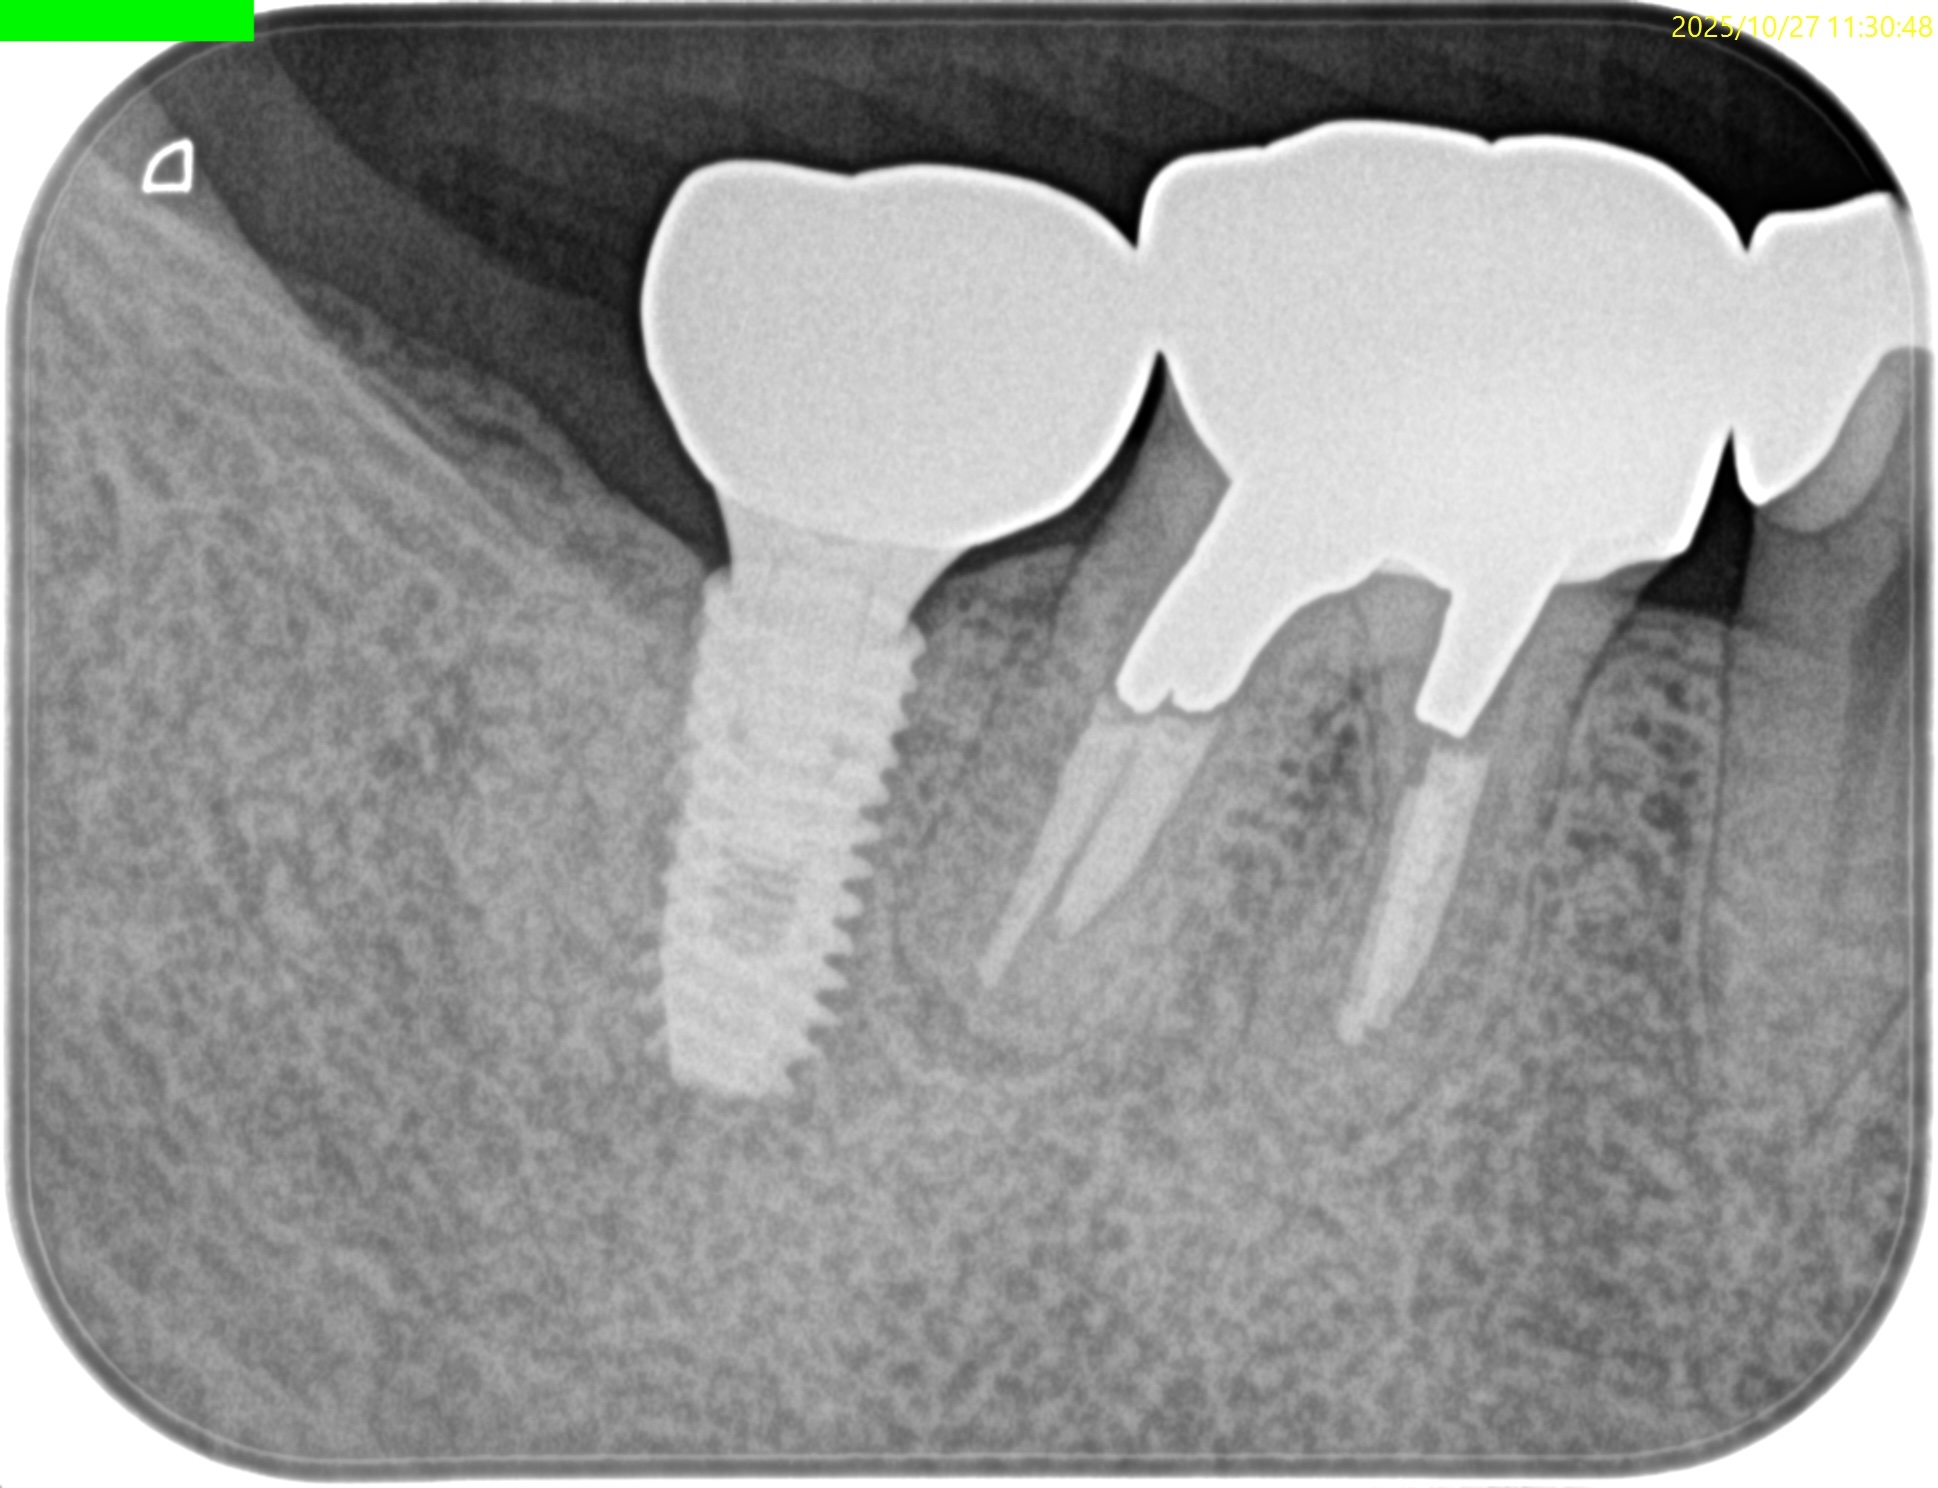

PA(2025.10.27)

近心はテーパー型、

遠心はパラレルで外れにくい感じのメタルポストコアだ。